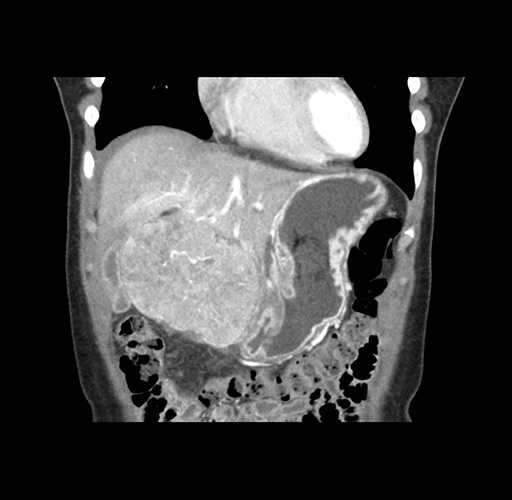

Imaging Analysis

Look through the patient's CT scan to identify any areas of concern for the necessary procedure.

Based on your CT findings, which issue(s) would give reason for "planned slowing down moment(s)" in this case?